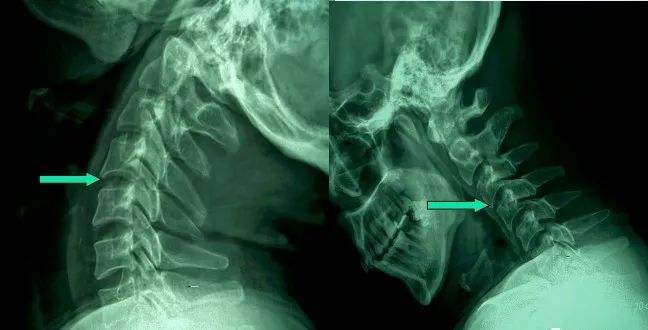

1、頸椎移位

由于頸椎關(guān)節(jié)突間關(guān)節(jié)面近乎水平位,一旦椎間盤發(fā)生退變、椎間隙即變窄,關(guān)節(jié)囊及韌帶松弛,加上頸部活動時(shí)重力的影響,即可造成積累性損傷,加速頸椎退變和不穩(wěn),導(dǎo)致頸椎關(guān)節(jié)發(fā)生移位,使椎間孔變狹,椎管徑發(fā)生改變,壓迫神經(jīng)根或脊髓,產(chǎn)生臨床癥狀與體征。